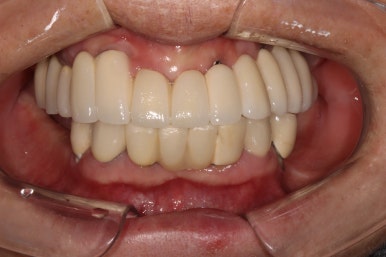

생각보다 임시치아보다 훨씬 매끈한 표면과 비슷한 색깔을 자랑하는 지르코니아 크라운입니다.

오스템 원가이드 네비게이션 임플란트 시스템을 이용하면, 정교하게 이상적인 위치에 임플란트를 심어낼 수 있어 자연스러운 임플란트 보철물을 제작하는데 많은 도움을 받을 수 있습니다!!

최종 완성된 보철물은 상당히 이상적인 형태를 갖고 있습니다.

이제 드디어 부분틀니를 쓰지 않아도 되는 ... 행복한 순간입니다.

치과용 파노라마 사진을 보면 뭔가 좌우 대칭으로 깔끔하게 완성된 아래턱 양쪽 어금니 임플란트를 보실 수 있어요!!

차이를 별로 못느끼실 수 있겠지만, 임플란트 보철물 완성 6개월 후 방문 때 구강내 사진입니다.

감사히도 환자분께서 상당히 깨끗하게 유지하고 계셔서, 잇몸에 염증하나 없이 너~무 보기 좋더라구요.